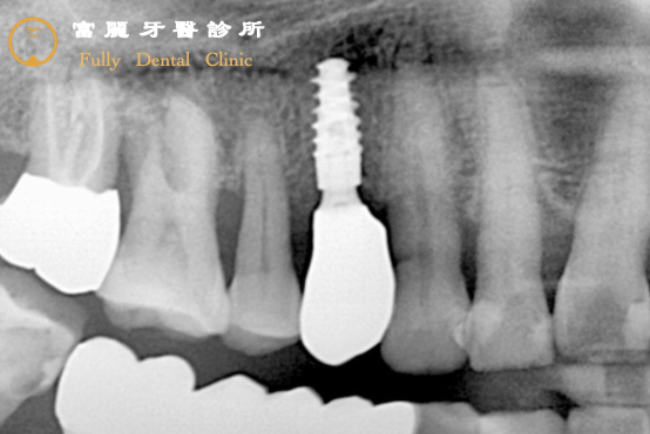

After

將牙根移除後,先填補上人工骨粉,讓剩餘的骨頭沿著人工骨粉生長回來;在缺牙處植入人工牙根(透過3D植牙導航儀植入深螺旋高階植體),再裝上擬真全瓷牙冠復形,以高穩定度與高強度的人工牙根和牙冠修復咬合功能,透過日常清潔和定期檢查,就像自己的牙齒重生一樣!